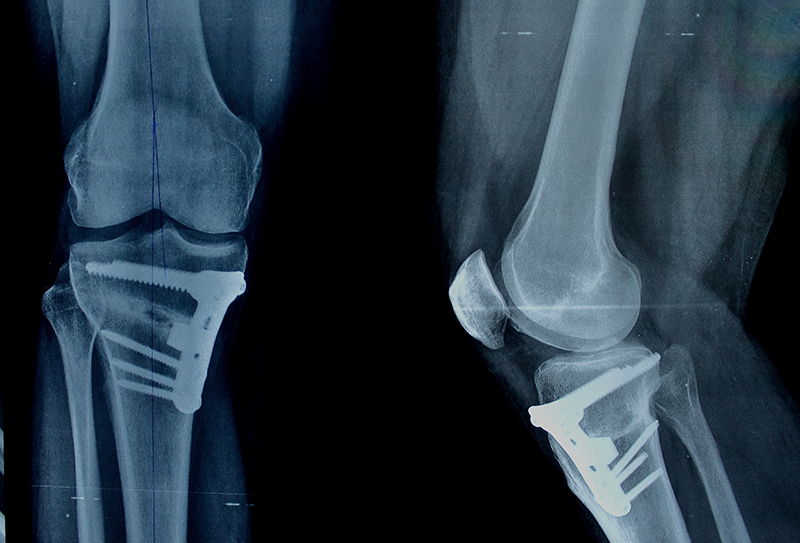

OSTEOTOMIE OKOŁOKOLANOWE - OSTEOTOMIE KOREKCYJNE

To zabiegi operacyjne w leczeniu wczesnej choroby zwyrodnieniowej stawu kolanowego lub nawet mających zastosowanie u pacjentów z zaawansowana chorobą zwyrodnieniowa st. kolanowego w pewnych grupach pacjentów, którzy nie godzą się na protezoplastykę. Procedura polega na przecięciu kości piszczelowej lub/i udowej, dzięki czemu można osiągnąć korekcję zaburzeń osi kończyny dolnej optymalizując rozkład sił działających na staw w efekcie dając zmniejszenie dolegliwości bólowych. Zabieg jest możliwy do wykonania u pacjentów w każdym wieku.

Wskazania do zabiegu to m.in. :

- szpotawość i koślawość statyczna i/lub dynamiczna st. kolanowego

- szpotawość i koślawość pourazowa st. kolanowego

- stan po resekcjach łąkotki przyśrodkowej lub bocznej

- jałowa martwica kostno-chrzęstna / uszkodzenia chrząstek st. kolanowego (jako zabiegu uzupełniający)

Przed przystąpieniem do zabiegu konieczna jest konsultacja z jednym z naszych lekarzy, który zbierze ogólny wywiad, oceni stan ogólny kliniczny pacjenta, wykona USG oraz zleci odpowiednie niezbędne badania - zwykle jest to rezonans magnetyczny st. kolanowego oraz RTG posturalne kończyn dolnych - pozwalające zaplanować szczegółowo operację.

Przebieg pozabiegowy: Jeszcze tego samego dnia pacjent jest usprawniany przy asyście fizjoterapeuty - nauka chodzenia o kulach łokciowych z markowanym obciążaniem kończyny operowanej wraz z ćwiczenia st. kolanowego w pełnym zakresie mające na celu jak najszybsze odzyskanie samodzielności. Czas w jakim pacjent wraca do aktywności sportowej wynosi około 3 miesiące. Czas spędzony w szpitalu wynosi 1-2 dni.